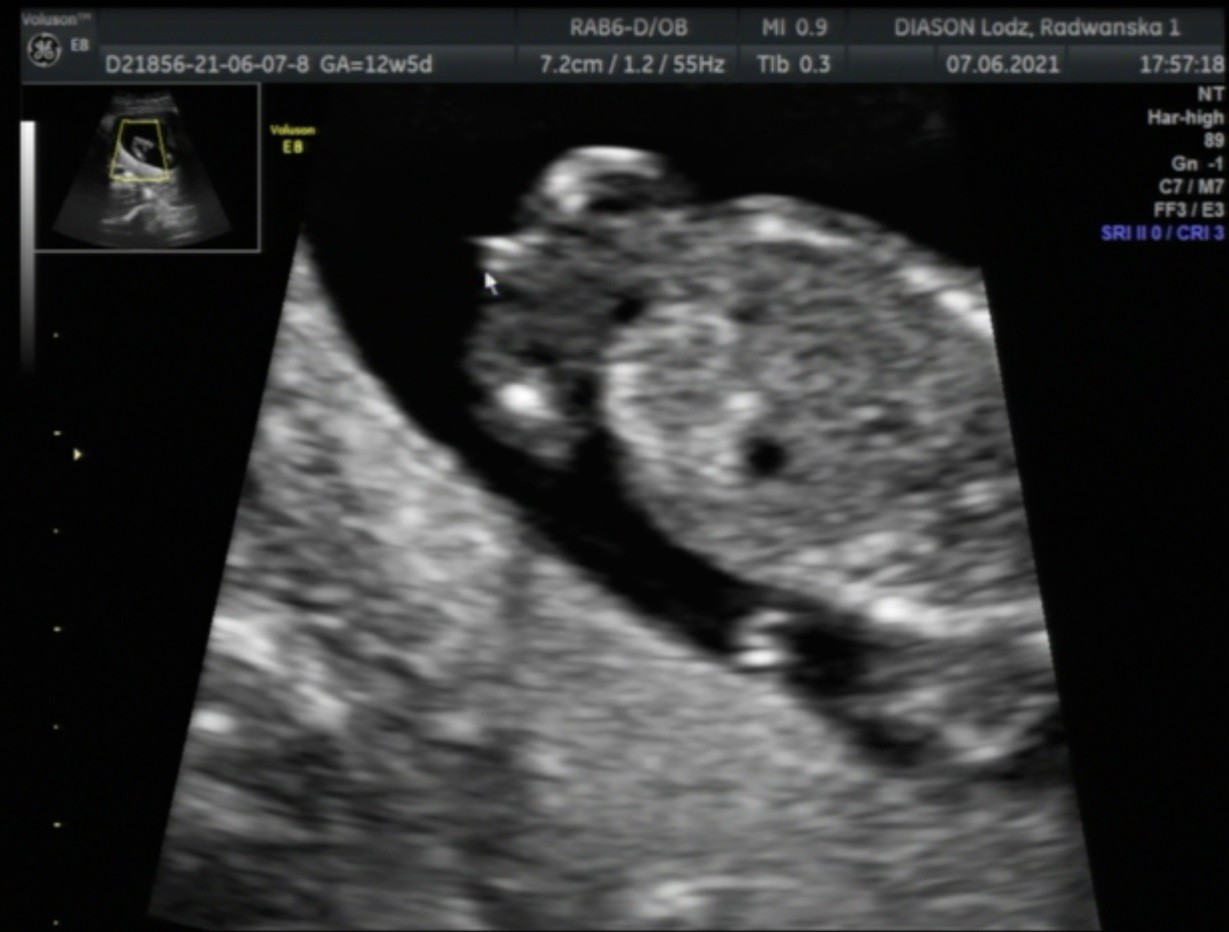

hej :) poprosze o Wasza ocene dziewczyny ! Jestem po usg 11-14tc, lekarz stwierdził że widzi zarowno mozliwa dziewczynke (zdjecie 1) jak i chlopca (zdjecie2). Oceńcie na podstawie waszych doswiadczen :) , kolejne usg za kilka tyg a za mna chodzi taka ogromna ciekawość .. :)

Dobrze Ci napisał , w tych tygodniach ciąży jedynie podczas pierwszego USG prenatalnego lekarz ocenia płeć po wyrostku , ale to musi być boczny przekrój ciała 🙂 podczas normalnej wizyty w tych tyg o których piszesz może wszystko się zmienić. Ja po moim przykładzie : USG prenatalne w 12 tc po wyrostku lekarz ocenił , że 80% dziewczynka, na normalnej wizycie moja doktor prowadząca w 14 TC pokazała mi siusiaka ja też go widziałam , a już w 17 TC siusiaka się wchłoną i zostały dwie bułeczki 😂💗 także jeszcze trochę cierpliwości 🙂🙂🙂